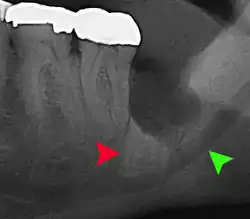

Long-term complications can include periodontal complications such as bone loss on the second molar following wisdom teeth removal. Bone loss as a complication after wisdom teeth removal is uncommon in the young but present in 43% of those of 25 years of age or older.[23] Injury to the inferior alveolar nerve resulting in numbness or partial numbness of the lower lip and chin has reported rates that vary widely from 0.04% to 5%.[23] The largest study is from a survey of 535 oral and maxillofacial surgeons in California, where a rate of 1:2,500 was reported.[26]

Coronectomy

Coronectomy is a procedure where the crown of the impacted wisdom tooth is removed, but the roots are intentionally left in place. It is indicated when there is no disease of the dental pulp or infection around the crown of the tooth, and there is a high risk of inferior alveolar nerve injury.[32]

Coronectomy, while lessening the immediate risk to the inferior alveolar nerve function has its own complication rates and can result in repeated surgeries. Between 2.3% and 38.3% of roots loosen during the procedure and need to be removed and up to 4.9% of cases require reoperation due to persistent pain, root exposure or persistent infection. The roots have also been reported to migrate in 13.2% to 85.9% of cases.[32]